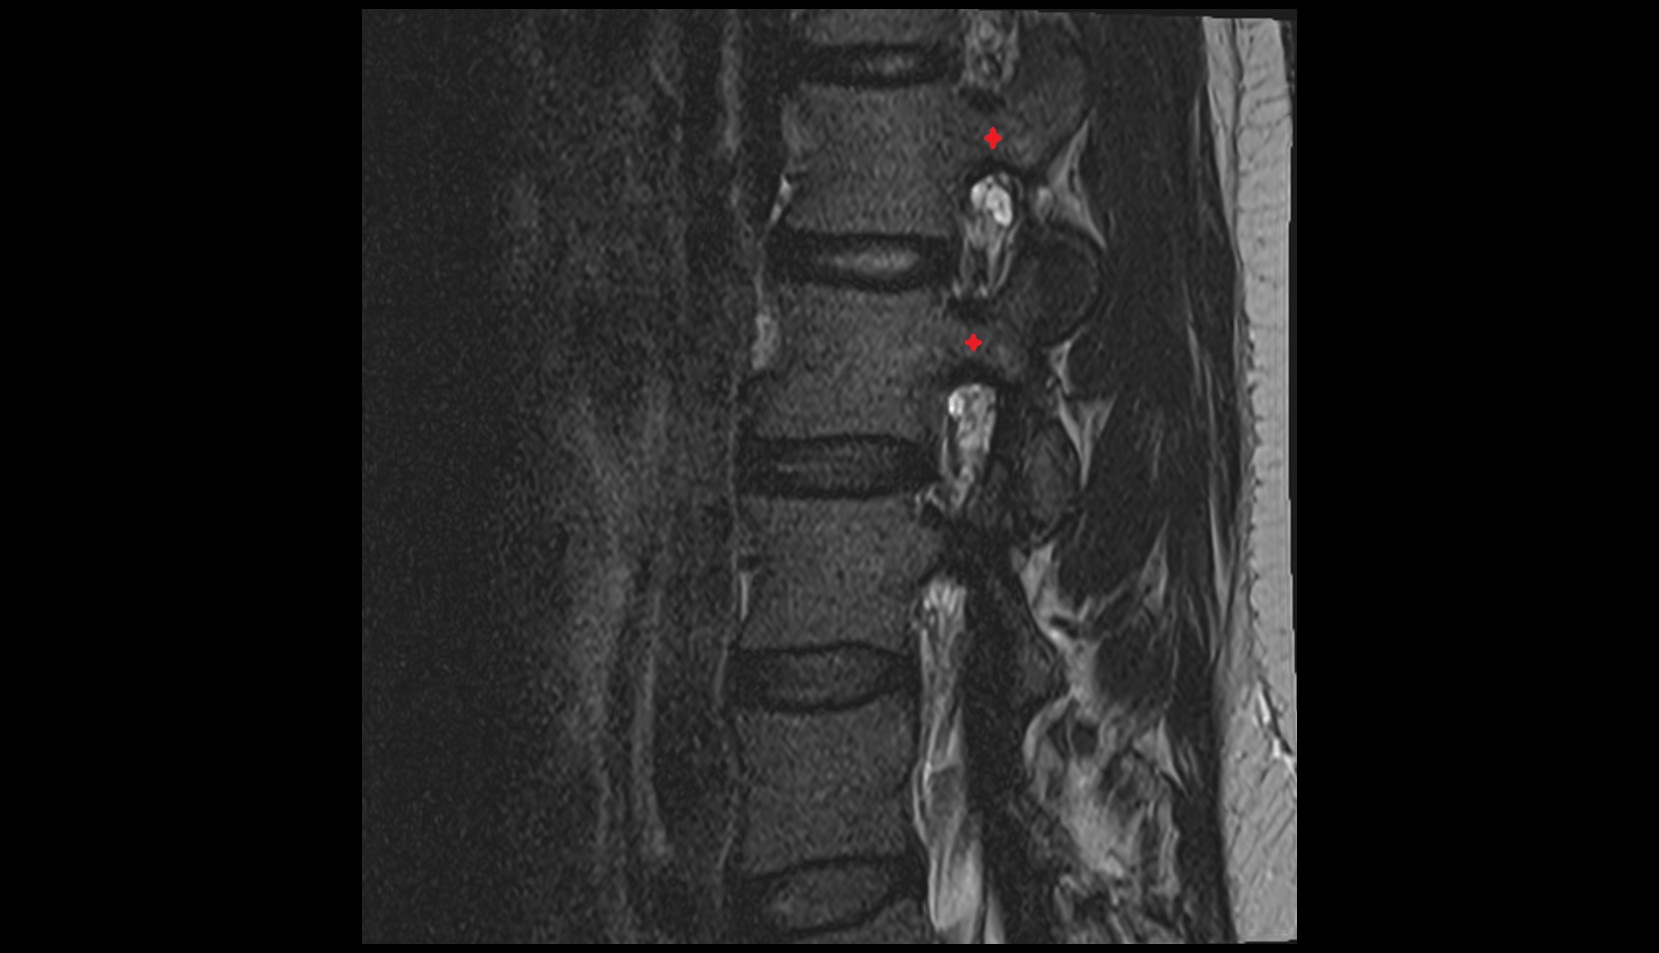

- L4–L5 Intervertebral Disc

- L3–L4 Intervertebral Disc

- Annulus fibrosus of intervertebral disc

- Spinal dura mater

- Spinal epidural space